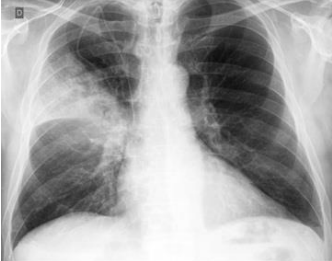

Podemos observar, nitidamente, nesta radiografia, um infiltrado à direita, compatível com uma consolidação lobar, o que configura: